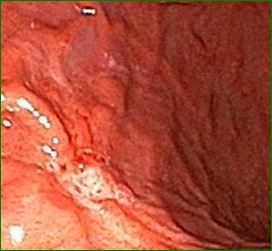

헬리코박터균이란?

헬리코박터균은 인간 위에 주로 서식하는 세균으로, 전 세계 인구의 절반 이상이 감염되어 있다고 알려져 있어요. 하지만 증상이 전혀 없는 경우도 많아서 몰래 숨어 지내는 고수 같은 존재랍니다. 그렇다고 방심하면 안 돼요!

복통, 메스꺼움, 소화불량 같은 증상으로 갑작스럽게 등장할 수 있거든요.